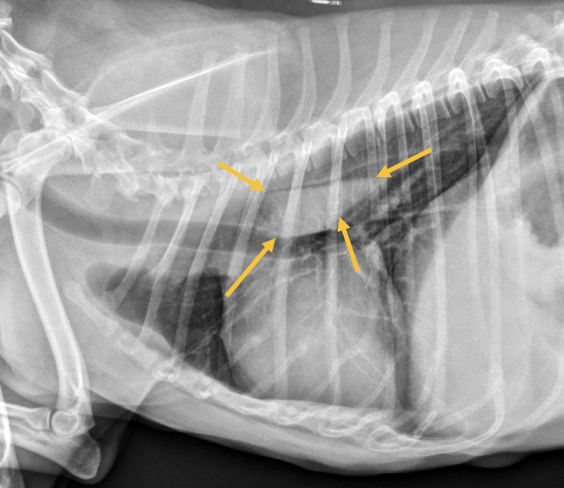

11

Esophageal dilation

Arrow = tracheal stripe